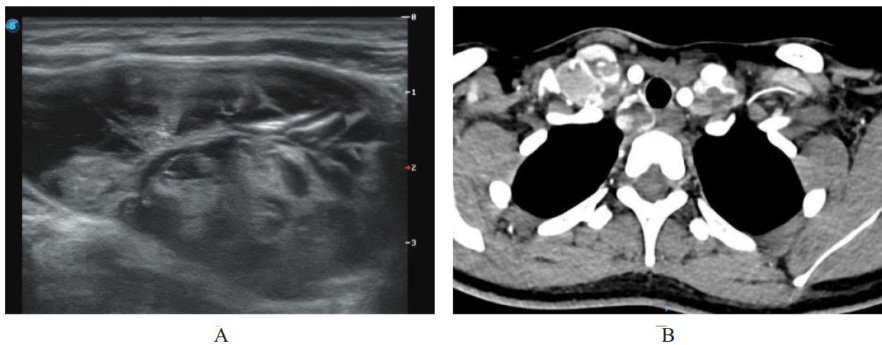

ABSTRACTFollcular variant papillary thyroid carcinoma (FVPTC) is commonly found in young middle-aged women, cases in children adolescents are relatively rare.The main driving genes FVPTC are the RAS oncogene family or B-Raf proto-oncogene serine/threonine protein kinase (BRAF) , DICERl gene mutation is rarely reported in this subtype.This article reports a case recurrentFVPTC with positive DICER1 mutation in an adolescent,aiming to provide reference for the clinical diagnosis treatment FVPTC.The patient,a 19-year-old female,underwent total thyroidectomy central lymph node dissection due to thyroid nodules 5 years ago, was pathologically diagnosed with follcular tumor uncertain malignant potential (FT-UMP);after surgery,the patients did not regularly undergo thyroid-stimulating hormone (TSH) suppression therapy follow-up as instructed. Two months ago,the patient visited the hospitaldue to enlarged cervical lymph nodes,imaging suggested tumorrecurrence with metastases to both lungs vertebrae, multigene testing indicated a DICER1 gene mutation. After comprehensive multidisciplinary consultation,bilateral cervical lymph node dissection was performed, postoperative pathology confirmed the diagnosis metastatic FVPTC. Te clinicans should focus on rare gene mutations such as DICER1 in the FVPTC patients, for adolescent patients,follow-up formulation individualized treatment plans should be emphasized to achieve early tumor identification precise intervention, improve the long-term prognosis patients.

滤泡亚型甲状腺乳头状癌(follicularvariantpapillarythyroidcarcinoma,FVPTC)好发于中青年女性,在儿童及青少年中相对罕见,相关临床资料较为有限[。(剩余10651字)